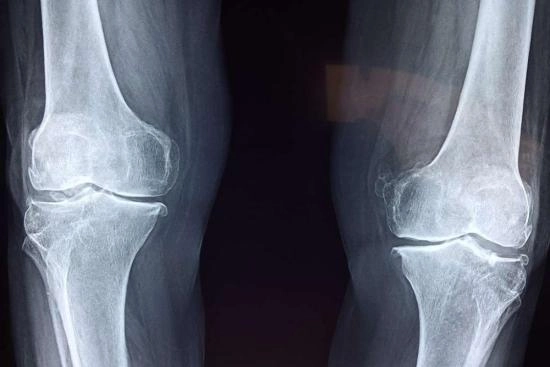

كيف نفرق بين الأسباب المختلفة لألم العظام؟

التمييز بين الأسباب المختلفة لألم العظام يبدأ أولًا من وصف المريض لتفاصيل الألم: متى بدأ؟ هل هو مستمر أم متقطع؟ هل يزداد مع الحركة أم في وقت الراحة؟ هذا النوع من المعلومات يساعد الطبيب على رسم ملامح أولية للتشخيص؛ فالألم الناتج عن إصابة، مثل الكسر أو الرض، يكون في المعتاد حادًا ومفاجئًا ويزداد مع الحركة، بينما الألم الناتج عن ورم أو التهاب مزمن يكون أكثر خفاءً ويزداد تدريجيًا مع مرور الوقت، وربما لا يرتبط بنشاط بدني واضح.

إلى جانب طبيعة الألم تلعب الأعراض المصاحبة دورًا كبيرًا في توجيه التشخيص مثلًا وجود تورم أو احمرار في موضع الألم قد يشير إلى التهاب، بينما فقدان الوزن أو التعب المستمر قد يكونان علامة على مرض خبيث مثل الورم أو مرض في الدم؛ كما تعتبر الفحوصات التشخيصية عاملًا حاسمًا، إذ تستخدم تحاليل الدم للكشف عن مؤشرات الالتهاب أو نقص الفيتامينات، بينما تُظهر الأشعة السينية أو الرنين المغناطيسي وجود كسور خفية، أو تغيرات في نسيج العظم، أو حتى كتل غير طبيعية؛ بناء على كل هذه المعطيات، يمكن الوصول إلى تشخيص دقيق وخطة علاج مناسبة لكل حالة.